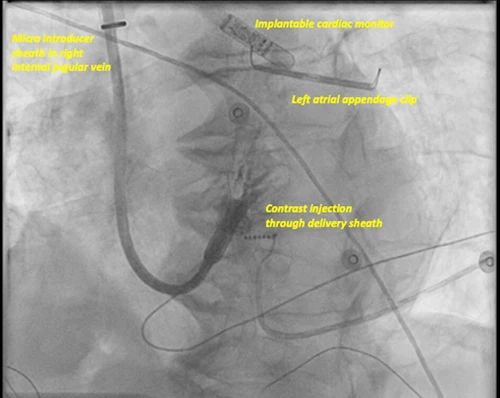

图4、上腔静脉入路

患者既往有外科房颤消融和左心耳结扎术史,存在反复静脉血栓和慢性下腔静脉滤器阻塞。推荐植入LP和房室结消融术。左前斜位通过输送导管注射造影剂显示导管头端紧靠右室中位间隔部。